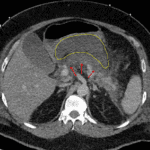

- Hypoenhancement of the pancreatic body as well as of portions of the head and tail

- Peripancreatic collection in lesser sac measuring 13 x 8 x 9 cm

- Necrotizing pancreatitis

Acute necrotizing pancreatitis with an acute necrotic collection in the lesser sac, which should be more accessible to endoscopic rather than percutaneous drainage. No gas is identified within this collection.

No evidence of associated vascular complication.